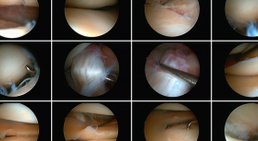

Als Facharzt für Orthopädie und Orthopädische Chirurgie habe ich mich auf die Behandlung von Verletzungen und Erkrankungen des Fußes, des Knies und der Hüfte spezialisiert.

Arthroskopie (Sprunggelenk, Knie)